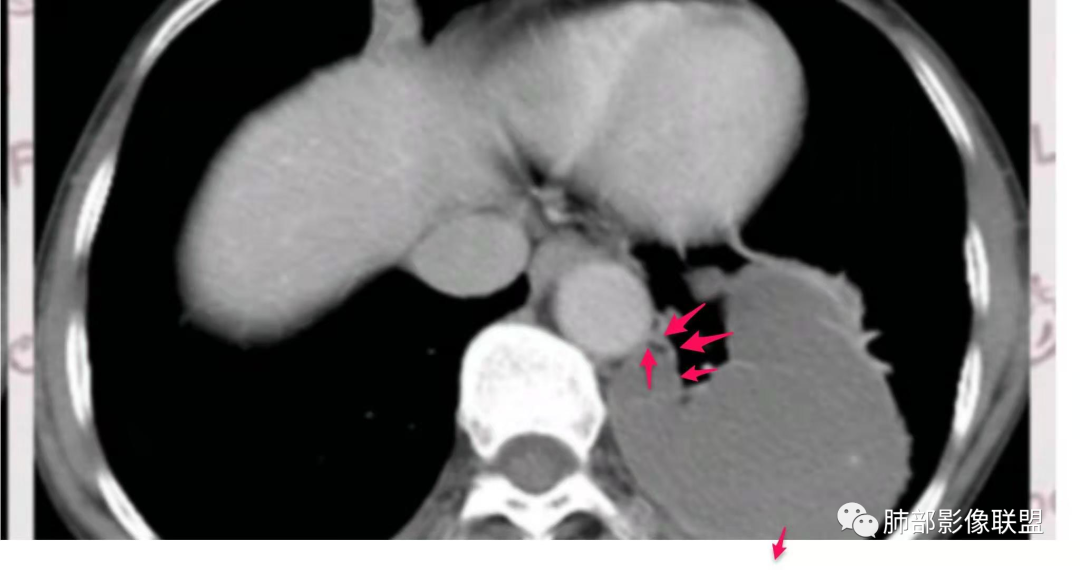

隔离常规是要考虑的,我需要看到供血血管

如果明确不是体循环供血

膈下的体动脉供血

体循环供血

这种常规来说,供血血管是非常清晰的。

就是一个体循坏的膈下的供血,我为什么考虑先天性的,我觉得左下肺是变小的。

我担心的是有些恶心肿瘤的,它也可以是体循坏供血。

但是这么明显的少,放个待排吧,首先选择隔离征吧。

供血:体动脉供血,多来自胸主动脉下部或腹主动脉上部,较为粗大,直径0.5~2cm,异常动脉多在下肺韧带内,经下肺韧带到达病变部位